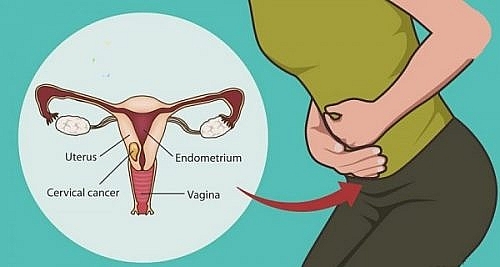

Các giai đoạn ung thư cổ tử cung

Ung thư cổ tử cung gồm các giai đoạn nào? Triệu chứng của ung thư cổ tử cung là gì? Cần làm gì để phòng tránh ung thư cổ tử cung?

18 tuổi có bị ung thư cổ tử cung không?

Ở bất kỳ độ tuổi nào cũng có nguy cơ bị ung thư cổ tử cung, tuy nhiên liệu 18 tuổi có bị ung thư cổ tử cung không? Cùng giải đáp câu hỏi này trong bài viết!

Bị ung thư cổ tử cung sống được bao lâu?

Bị ung thư cổ tử cung sống được bao lâu là câu hỏi mà rất nhiều bệnh nhân khi nhận được kết quả rất quan tâm. Khám phá ngay câu trả lời tại bài viết sau.

10 dấu hiệu ung thư cổ tử cung

Ung thư cổ tử cung là loại ung thư dễ gặp nhất ở phụ nữ. Cùng khám phá ngay 10 dấu hiệu ung thư cổ tử cung thường gặp để phòng tránh an toàn nhé!